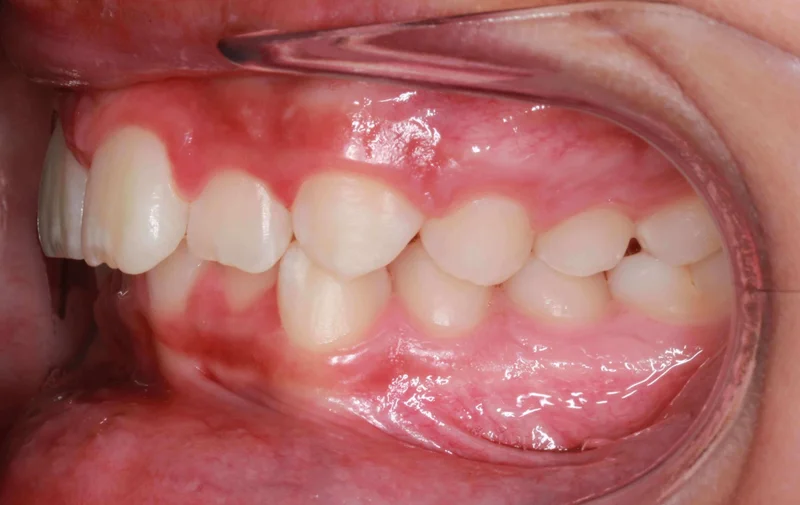

Left Buccal View

Left Buccal View - Before Treatment

Before